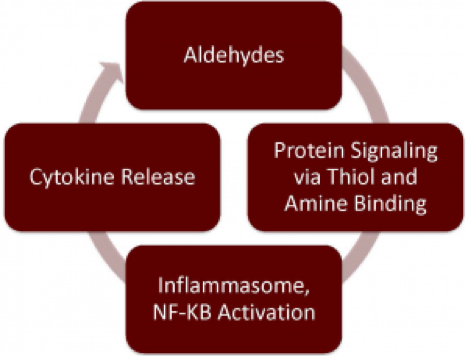

Image Source: https://www.aldeyra.com/our-novel-platform/

It seeks to leverage its understanding of Reactive Aldehyde Species (RASP) levels to tackle intracellular inflammatory factors including NF-kB, a prominent protein in the inflammatory response. Its reproxalap can bind to free aldehydes triggering a covalent reproxalap-aldehyde adducts that can degrade intracellularly within hours with significant lowering of aldehyde levels.